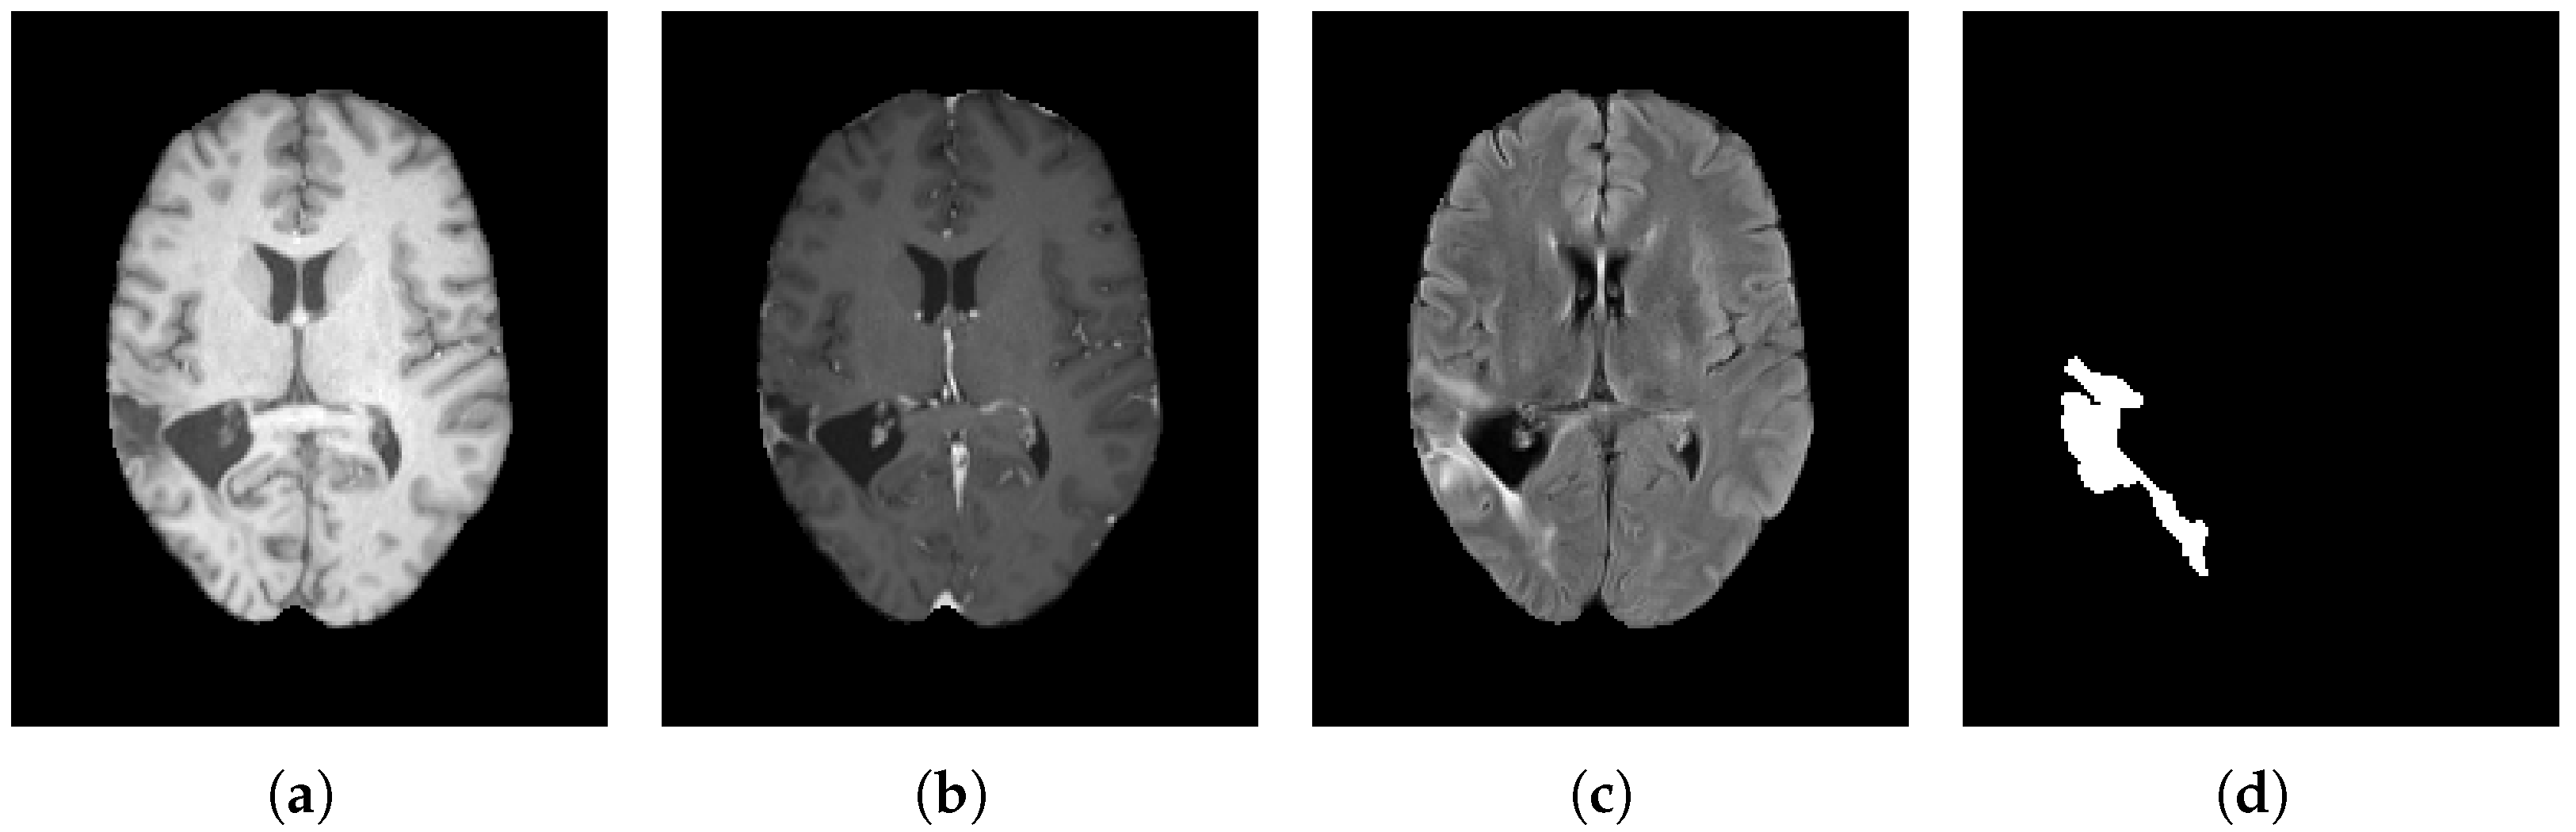

MRI encompasses various complementary modalities: T1, T1-C, T2, and FLAIR [19]. Each imaging modality provides a comprehensive understanding of both the structural and functional tumor characteristics. T1-weighted imaging is used to highlight the anatomy and structure of the region under study. A bright appearance indicates the presence of fat, while fluids such as cerebrospinal fluid appear dark [20]. Similarly, T2-weighted images are susceptible to fluids and can detect inflammation, tumors, and lesions, as fluids appear bright in these images. Moreover, T1-weighted contrast (T1-C) uses a contrast agent to enhance tissue visibility, making abnormalities such as tumors and inflammation appear brighter [21]. Lastly, fluid-attenuated inversion recovery (FLAIR) uses T2-weighted images and suppresses cerebrospinal fluid to enhance the contrast between fluids and surrounding tissues, thus facilitating the detection of superficial brain lesions [22].

Figure 2 presents three imaging modalities (a–c) along with the corresponding ground-truth tumor mask (d). The purpose of displaying this tumor image is to illustrate which modality provides the most precise visualization of the tumor, with the T2-weighted MRI modality offering the most reliable depiction of the tumor core (see Figure 2c) while FLAIR provides complementary information on peritumoral edema and diffuse infiltration.